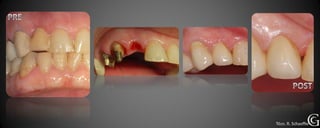

Prótesis Fija Convencional

Puentes

Los puentes son restauraciones que sirven para reemplazar piezas

perdidas, involucrando piezas vecinas. Son confeccionadas fuera

de la boca y luego adheridas o cementadas a los dientes vecinos a

a la pieza perdida.

Prótesis Fija Convencional Puentes Los puentes son restauraciones que sirven para reemplazar piezas perdidas, involucrando piezas vecinas. Son confeccionadas fuera de la boca y luego adheridas o cementadas a los dientes vecinos a a la pieza perdida.